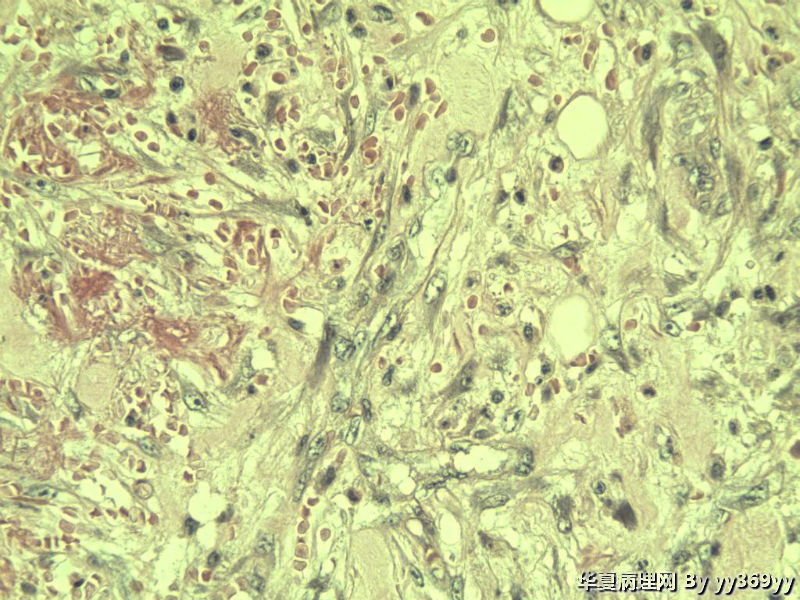

男 30岁 小肠一段,肠管严重粘连可见一体积为 2.5 × 2 × 1.5 cm3的肿块,切面灰白,实性,质中

小肠肿瘤图3

这些都是增生的神经节细胞,在溃疡周围的正常粘膜里找找看有无肉芽肿

考虑炎性肌纤维母细胞瘤、炎性纤维性息肉、胃肠间质瘤,不考虑淋巴瘤

考虑炎性肌纤维母细胞瘤

神经节细胞

补取了几块 肌层纵行和横行平滑肌之间很多这种细胞 是什么??